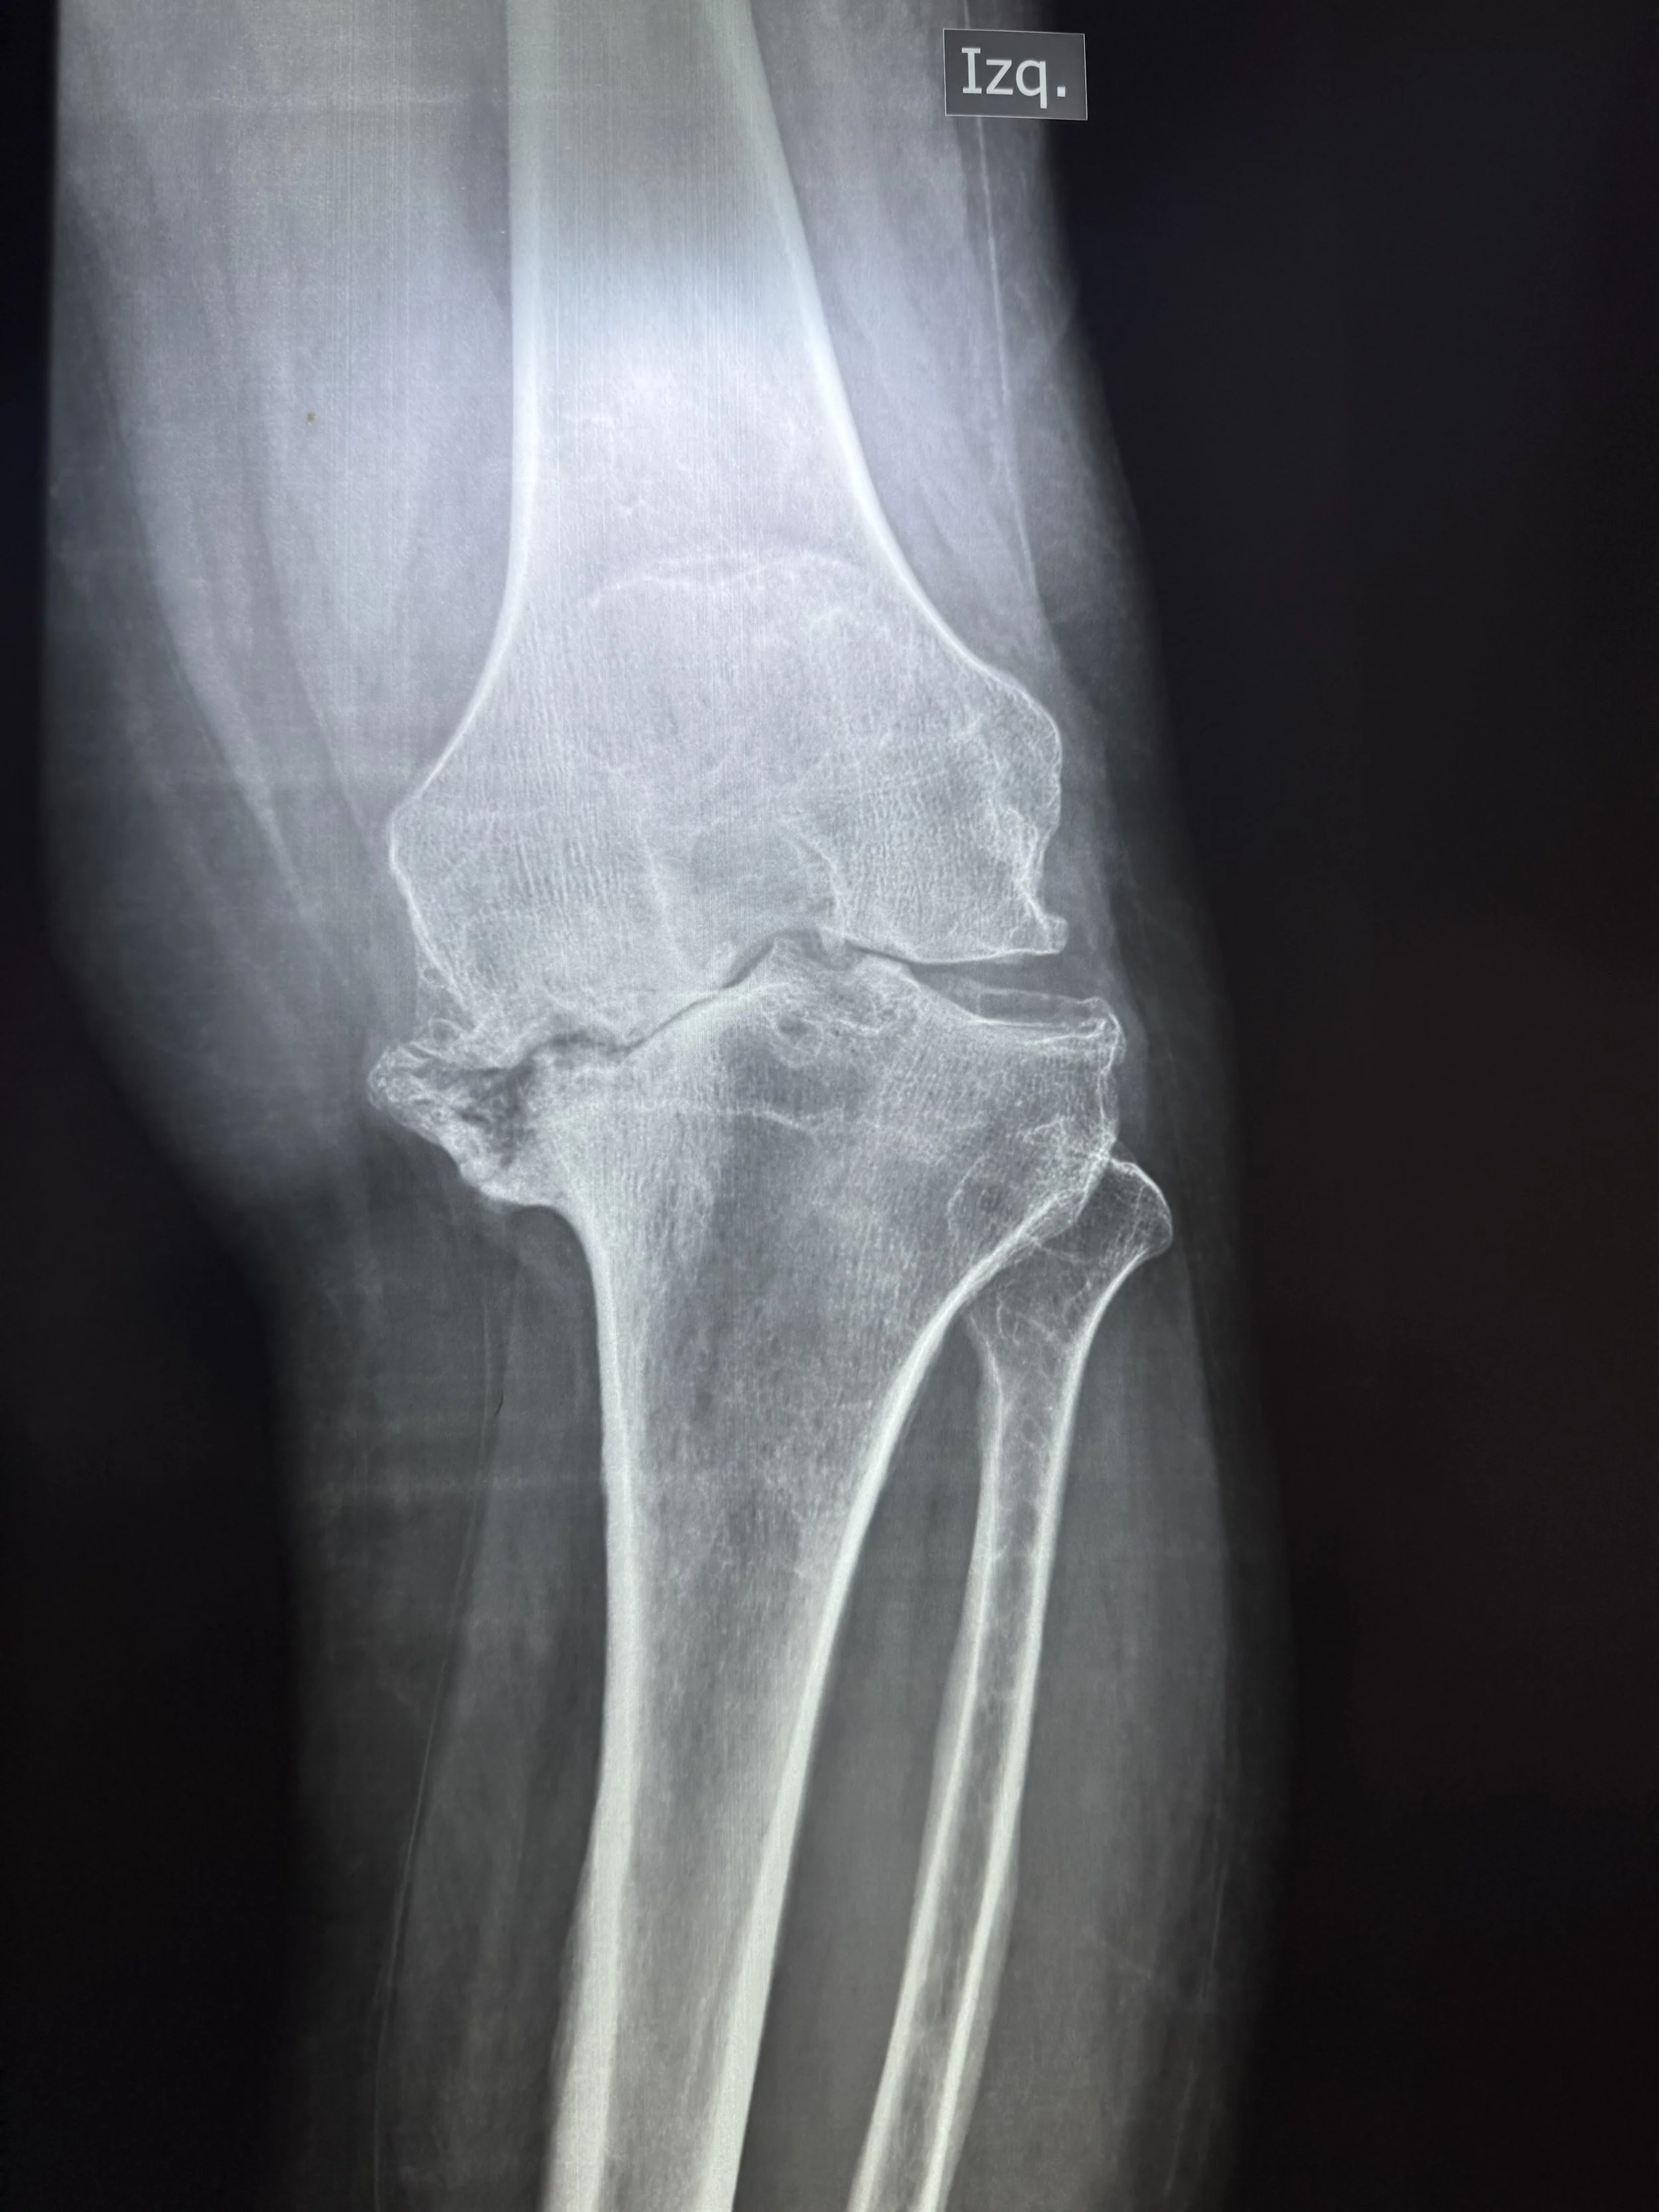

Today, we had the humble privilege of seeing over 100 patients in need of surgical care for hip, knee, foot, and ankle deformity. We will begin tomorrow with 6 operating rooms, 25 cases planned, 9 surgeons, 7 anesthesiologists, and 43 health care professionals working together.